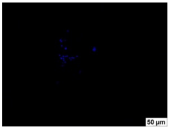

2.4. Evaluation of Macrophage Adhesion to the Surface of the Tested Samples

Following the investigation of cytotoxicity, the adhesion of macrophages to the surface of the examined samples was explored. In the experiments, it was observed that the number of adhered macrophages from the RAW 264.7 line on the surface of tablet wells without the investigated composite film materials in the microscope’s field of view was 355 ± 36 (Table 4). Upon placing RAW 264.7 cells in the tablet wells with the surface of the comparison sample “Seprafilm”, the number of adhered cells significantly decreased to 128 ± 16 within the microscope’s view field. The adhesion of macrophages on the surface of the composite film materials samples, based on the sodium salt of carboxymethylcellulose modified by allantoin (2, 3), did not differ significantly from the comparison sample “Seprafilm”.

The number of adhered cells in the microscope’s field of view was 215 ± 31 (p = 0.058) and 195 ± 29 (p = 0.064) cells, respectively. In contrast, the ability of macrophages to adhere in the samples of composite film materials based on glycoluril-modified sodium salt of carboxymethylcellulose (4, 5) was significantly lower than in sample (1) and the studied samples (2, 3). The number of adhered cells in the microscope’s field of view was 61 ± 8 and 18 ± 5, respectively.

Consequently, the tested composite film materials samples, which are based on allantoin-modified sodium salt of carboxymethylcellulose (2, 3), exhibit a diminished ability for macrophages from the RAW 264.7 line to adhere, and their adhesion value is comparable to that of sample (1).

The samples of composite film materials, derived from the glycoluril-modified sodium salt of carboxymethylcellulose (4, 5), exhibit notably reduced adhesion of RAW 264.7 line macrophages to the surface compared to both sample (1) and the examined composite film materials based on allantoin-modified sodium salt of carboxymethylcellulose (2, 3).

3.4. Adhesion of Macrophages to the Surface of the Tested Samples

Following the investigation of cytotoxicity, the adhesion of macrophages to the surface of the examined samples was scrutinized. Experimental results revealed that the number of adhered macrophages of the RAW 264.7 line on the surface of tablet wells lacking the investigated composite film materials within the microscope’s field of view was 355 ± 36 (Table 4). Upon placing RAW 264.7 cells in the wells of the tablet on the film surface of the comparison sample “Seprafilm”, the number of adhered cells significantly decreased to 128 ± 16 in the microscope’s field of view. The extent of macrophage adhesion on the surface of the samples of composite film materials based on allantoin-modified sodium salt of carboxymethylcellulose (2, 3) did not differ from sample (1), with the number of adhered cells in the microscope’s field being 215 ± 31 (p = 0.058) and 195 ± 29 (p = 0.064), respectively. The ability to adhere macrophages in the samples of composite film materials based on glycoluril-modified sodium salt of carboxymethylcellulose (4, 5) was significantly lower than in sample (1) and the studied samples (2, 3), with the number of adhered cells in the microscope’s field being 61 ± 8 and 18 ± 5, respectively.

Hence, the samples of the examined composite film materials based on allantoin-modified sodium salt of carboxymethylcellulose (2, 3) exhibit a limited ability to adhere RAW 264.7 macrophages, and their adhesion capability is not inferior to that of sample (1). In the case of samples of composite film materials based on glycoluril-modified sodium salt of carboxymethylcellulose (4, 5), the adhesion of RAW 264.7 macrophages to the surface is significantly lower compared to sample (1) and the investigated composite film materials based on allantoin-modified sodium salt of carboxymethylcellulose (2, 3).

The plates were subjected to a 24 h incubation at 37 °C in a 5% CO2 atmosphere. Following this, non-adherent cells were removed by resuspending the cell suspension. Cells attached to the surface of the composite film materials were subsequently fixed with 2.5% glutaraldehyde for 30 min and stained with fluorescent dyes, specifically Phalloidin-Atto-488 for cytoskeleton staining and DAPI for nucleus staining.

The count of cells adhered to the surface of the composite film materials within the microscope’s field of view was conducted utilizing a Leica DMi8 fluorescence microscope [40]. Three repetitions of experiments were carried out for each composite film sample and the comparison sample “Seprafilm”, with the number of adhered cells in each experiment assessed across three fields of view.